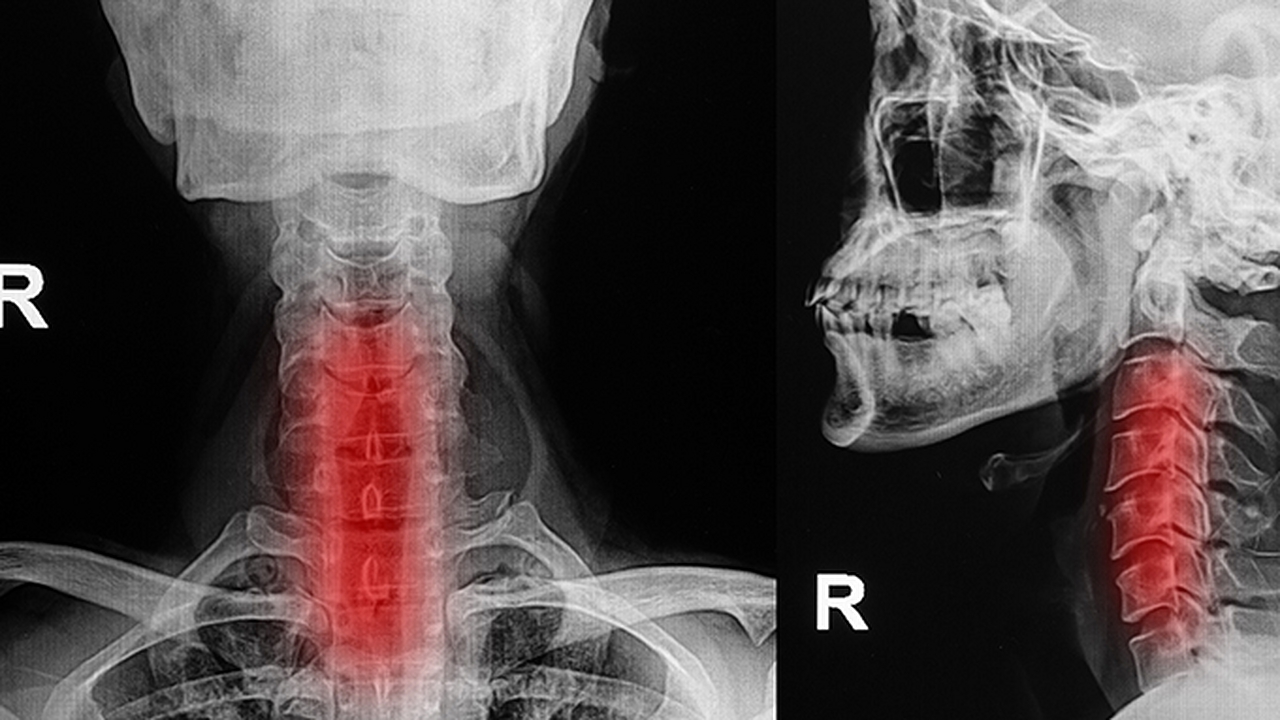

4、甲狀腺疾病

甲狀腺腫大可能壓迫氣管導致呼吸不暢,常見于結節(jié)性甲狀腺腫或甲狀腺功能亢進。需通過甲狀腺超聲和功能檢查確診。根據(jù)病因選擇左甲狀腺素鈉片或甲巰咪唑片等藥物治療,嚴重時需手術。